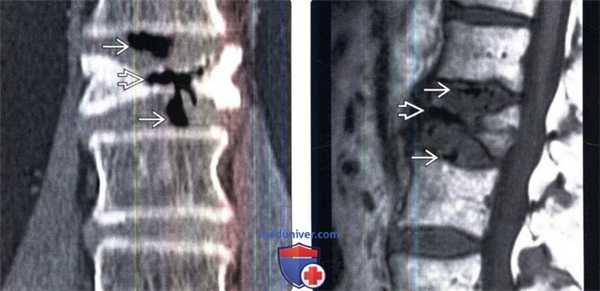

(Слева) На фронтальном КТ-срезе определяется накопление газа в коллабированном и склерозированием теле позвонка. Скопления газа также видны в смежных межпозвонковых дисках. Наблюдаемые при болезни Кюммеля скопления газа в телах позвонков возможно являются следствием его миграции из смежных дегенеративно измененных межпозвонковых дисков.

(Справа) Сагиттальный срез, Т1-ВИ: скопление газа в области взрывного перелома тела позвонка на фоне остеопороза и в толще смежных межпозвонковых дисков. Газ на МР-изображениях легко может быть ошибочно принят за очаги кальцификации.